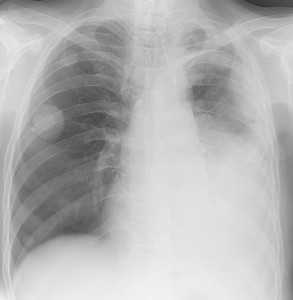

Слева - рак почки с метастазами в легкие, прогноз в данном случае неблагоприятный ввиду метастатического плеврита и дыхательной недостаточности. Определяются очаги с обеих сторон. Справа - мелко- и среднеочаговая диссеминация при раке печени.

Множественные гематогенные вторичные узлы при раке почки, компьютерная томография (КТ).